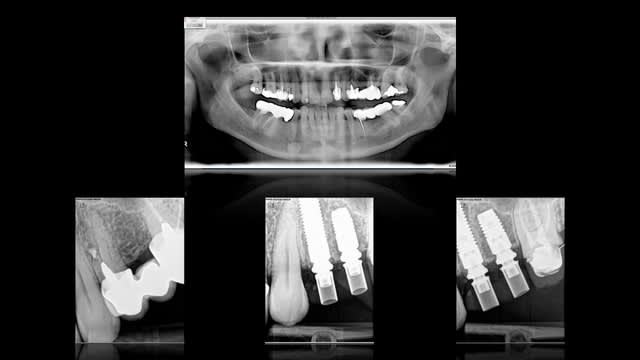

puisqu'il se passe pas grand chose en ce moment sur eugenol, voici un cas de ce matin.

- transformation du bridge pro en guide chir

- extraction 24

- mise en place d'implant en 24 et 25 : astra 4*13 et 4*8, comblement du gap au Bio-oss

- transformation du guide chir en bridge provisoire sur implant ( sur pilier uni )

désolé pour la qualité des radios et pour le bridge pro qui est pas térrible mais réalisé au fauteuil en un minimum de temps.